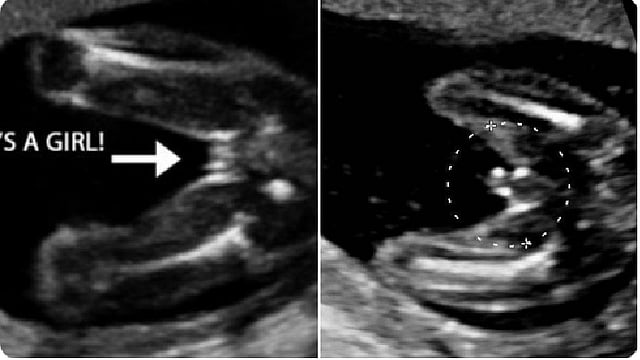

استشارية توضِّح أسباب خطأ السونار في تحديد جنس الجنين

أوضحت استشارية طب النساء والولادة، الدكتورة مها النمر، الأسباب التي تؤدي إلى خطأ السونار في بعض الأحيان في تحديد جنس الجنين.

وأشارت في تغريدة عبر حسابها الرسمي على تويتر، إلى أن تحديد جنس الجنين يعتمد على رؤية الأعضاء التناسلية بالأشعة.

ولفتت النمر إلى أن ذلك يعتمد على عدة عوامل تشمل:

1 - نوعية جهاز الأشعة «متطور/قديم».

2 - وزن المرأة «نحيفة/ممتلئة».

3 - وضعية الجنين.

4 - خبرة الطبيب.